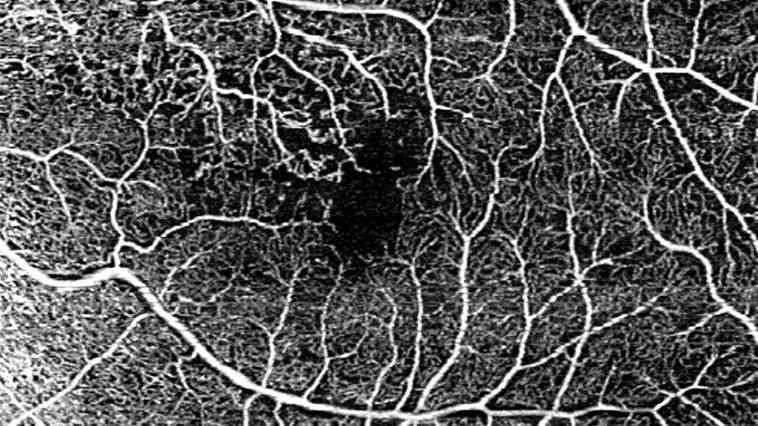

• 12x12 mm single-shot OCTA of branch retinal vein occlusion (BRVO)

12x12 mm single-shot OCTA of branch retinal vein occlusion (BRVO).

Image courtesy of Jesse Jung, MD, East Bay Retina, United States